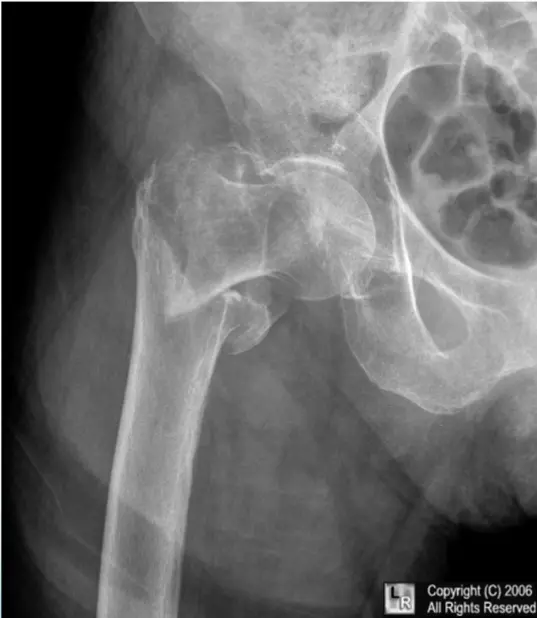

Patient: 46âyearâold lady

Incident: Fell two steps down the stairs and is now unable to stand.

Oncologic history: Breast carcinoma previously treated with chemotherapy and radiotherapy.

Fracture details

- Site: Upper shaft of the femur

- Type: Simple fracture

- Fracture line: Oblique crossing a lytic lesion â appears atypical

- Displacement: Medial shift with some overlap

- Special considerations: Pathological fracture related to metastatic disease

46âyearâold woman who slipped two steps down the stairs and was unable to stand.

She has a history of breast carcinoma treated with chemotherapy and radiotherapy.

- Location: Upper shaft of the femur

- Fracture line: Strange? (unusual pattern)

- Displacements:

- Medial shift

- Overlap

Special considerations: Pathological fracture (related to underlying disease).